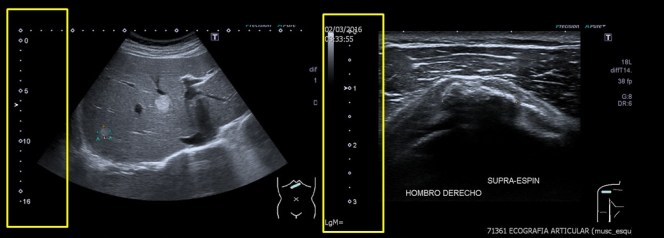

La profundidad es un ajuste ecográfico en el cual vamos a poder controlar la distancia a la que queremos trabajar o la distancia que necesitamos en centímetros para estudiar aquella estructura que deseemos. Por ejemplo, usaremos profundidades muy diferentes para estudiar un tendón supraespinoso o de un hígado.

Para estudios superficiales como pueden ser ecografías musculares o de partes blandas emplearemos profundidades pequeñas de máximo 4 cms para un paciente estándar, pero para estudiar el Abdomen de un adulto necesitamos perentoriamente utilizar profundidades de unos 15 cms…

Imágenes de Hígado y Tendón del Supraespinoso y sus profundidades de estudio en rectángulo amarillo.